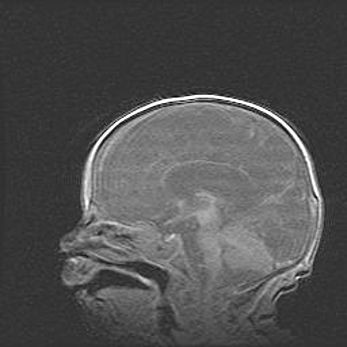

Открытая гидроцефалия.

Возраст: 6 месяцев 15 дней

Вес: 6200 г

Пол: женский

Окружность головы: 41 см

Срок гестации: 38 недель

Гидроцефалия головного мозга у новорожденных – это скопление избыточного количества цереброспинальной жидкости в головном мозге. Ее избыточное скопление в мозге приводит к патологическому расширению желудочков мозга (четырех полостей, расположенных в глубине белого вещества мозга, заполненных цереброспинальной жидкостью и связанных узкими проходами).

Открытый тип гидроцефалии (сообщающаяся) наблюдается тогда, когда нарушен механизм всасывания ликвора в системный кровоток. При этом типе причиной заболевания чаще всего является перенесенные ранее инфекции (например: менингит),  либо же наличие крови в субарахноидальном пространстве.